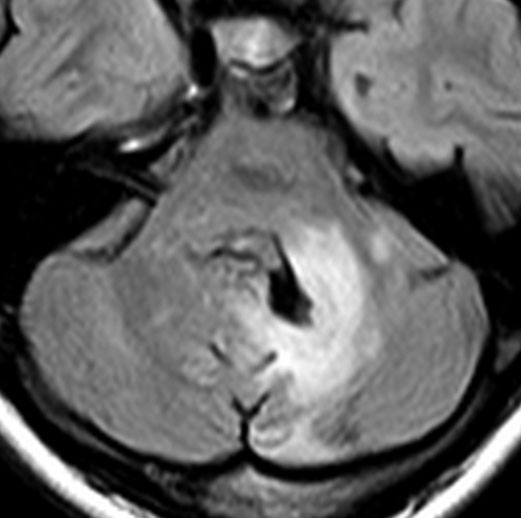

眼窩内に限局する視神経膠腫:神経鞘腫と鑑別が難しいもの

主訴は進行性の眼球突出です。視力低下は軽度で,視野欠損は左眼の下半分でした。入院前の画像では眼窩内神経鞘腫を疑う画像でした。

しかし,CISSの画像では中枢側の視神経との連続性があり,これではじめて視神経膠腫と診断できました。もちろん毛様細胞性星細胞腫です。眼球,眼球運動,眼瞼の動きを温存して腫瘍を眼球後極から切断して全摘出しました。